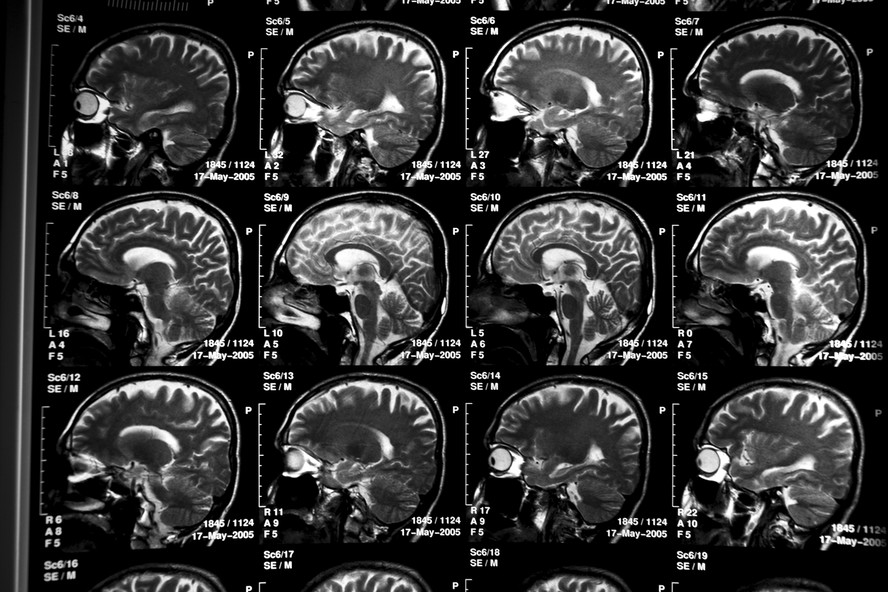

Exames de cérebro de paciente com Alzheimer. — Foto: Todd Heisler/The New York Times RESUMOSem tempo? Ferramenta de IA resume para você

Exames de cérebro de paciente com Alzheimer. — Foto: Todd Heisler/The New York Times